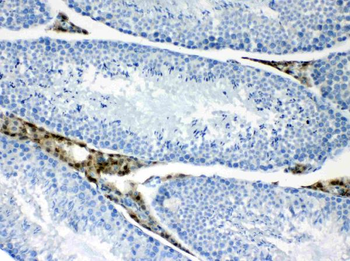

10 μg, 100 μg - Anti-HSD11B2 Antibody [orb316541]

IF, IHC, IHC-Fr, WB

Human, Mouse, Rat

Rabbit

Polyclonal

Unconjugated

10 μg, 100 μg - Anti-CD44 Antibody [orb402179]